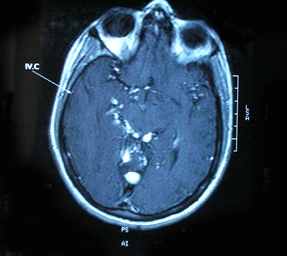

Mrb hocam..bir yakinimin mr sonucu soyle: sağ kaudat nükleus superior komşuluğunda lateral ventrikül frontal hornu komşuluğunda lateral ventrikul frontal hornu komşulugunda yaklaşık 15×10 mm boyutunda santrali BOS ile izointens periferinde FLAİR ağırlıklı sekansta hiperintens gliozis ile uyumlu alan bulunan lezyon dikkati çekmistir ( laküner infarkt? kistik lezyon?)

Serebellar tonsiller foramen magnumdan inferiora dogru yaklasik 6 mm lik herniasyon gostermektedir

Bas donmesi ile doktora gitmistik. Vertigo dedi..mr sonucu bu sekilde cikti.dogustan olabilir dedi.olmus bitmis birsey dedi. Sizin yorumunuz nedir hocam ardimci olur musunuz?